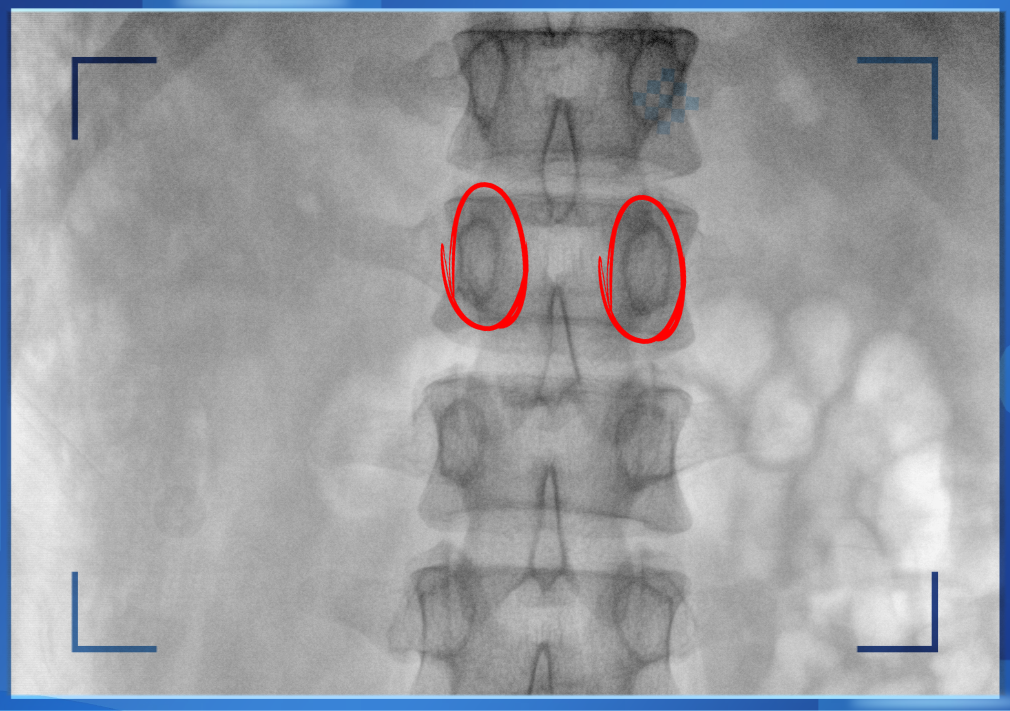

醫生通常會在“貓眼”里尋找進針點和出針點,憑醫生的經驗把釘子打在椎弓根里。手術比較依賴醫生的經驗,萬一出現偏差對病人來講就是毀滅性的打擊。如果在復雜的手術中有三維影像的支持,確保釘子精準的打在椎弓根里,可大大的提高手術操作的精度。

“貓眼”指的是椎弓根在正位的投影。